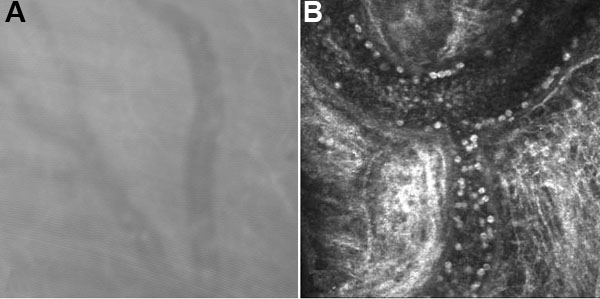

Figure 1.

Non-enhanced, representative images of ocular vessels obtained from A the ASL-1000 white light scanning confocal microscope (Advanced Scanning Ltd, New Orleans, LA) and B the HRTII laser confocal microscope (Heidelberg Engineering, Germany). Magnification of both images was 400X.